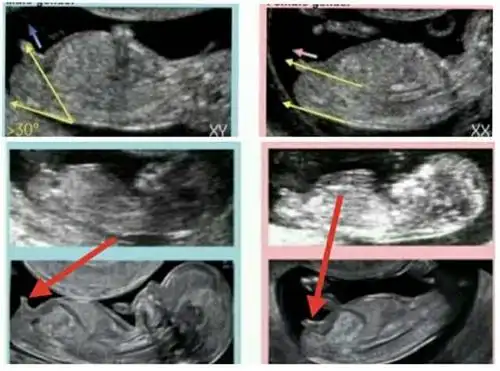

广州妈妈告诉你两张b超图片便可提前知道是男是女